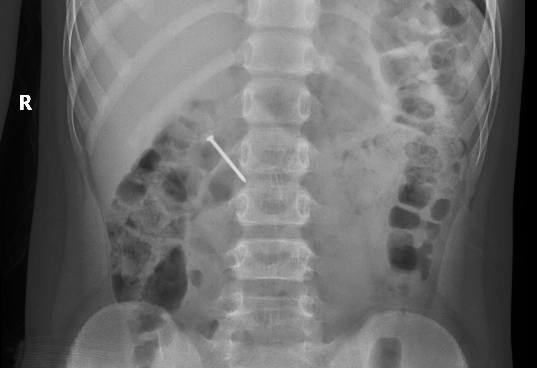

Kết quả chụp X-quang cho thấy chiếc đinh nằm trong lòng tá tràng bệnh nhi. Bác sĩ chỉ định phẫu thuật mở tá tràng lấy dị vật cho trẻ.

| Đinh sắt nằm trong tá tràng bệnh nhi. |

Do chiếc đinh nằm ở giữa tá tràng và sau phúc mạc nên ca phẫu thuật lấy dị vật tương đối khó khăn. Khi mổ, các bác sĩ kiểm tra không có tổn thương ruột nên đã lấy đi và khâu lại tá tràng cho bệnh nhi. Bé tiếp tục được theo dõi tại khoa Gây mê hồi tỉnh.